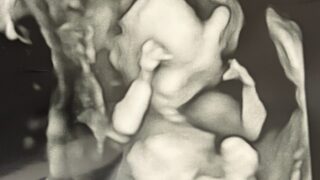

妊娠19週、毎週続いた大量出血が初めて止まり、血腫が小さくなった日の記録。足が短いと言われた時の不安、心臓エコーの結果、低身長症の治療について調べたことを、心の揺れとともに丁寧にまとめました。

🌿【妊娠18週】大腿骨が短い…

妊娠18週で「大腿骨が短い(−3.2SD)」と言われ不安でいっぱいに。胎児スクリーニングの結果、染色体異常の可能性、羊水検査の選択、もう一人の先生の診察で分かった「脳に異常なし」という安心材料まで、同じ経験をしている妊婦さんに向けて正直に記録しました。